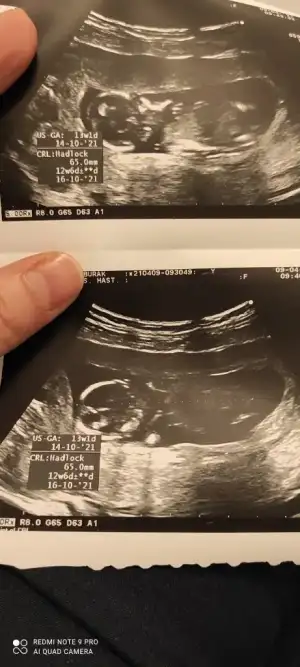

Ikra meyra Ikra meyra 12+1 sata göre bana da bakar mısınız çok hareketli oldugu için bişey demedi Dr

• IMG_20210409_103243.webp

IMG_20210409_103243.webp

41,4 KB · Görüntüleme: 65

• IMG_20210409_103239.webp

IMG_20210409_103239.webp

30,5 KB · Görüntüleme: 78